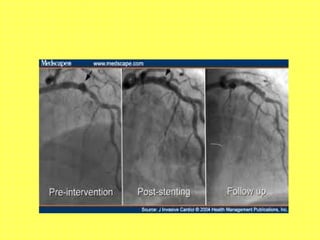

ARTERIOGRAPHY

Helps specially in in arteries that cannot be

biopsied easily like Aorta, Coronary artery,

Mesentric vessels

Presence of vascular patency, Aneurysms

• Aortic Angiography- Takayasu’s

• Cerebral Angiography- Isolated CNS vascultis

• Renal Angiography- PAN

• Coronary Angiography- Kawasaki’s

• Lower limb arteriography-Buerger’s Disease

(TAO)